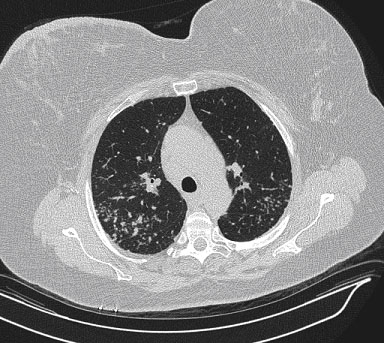

Chest CT: Multiple nodules smaller than a centimeter in diameter were present in both lungs with a perilymphatic distribution. A right paratracheal lymph node measured 1.9 cm. There was a 1.3 cm right precarinal lymph node, a 1.4 cm left anterior mediastinal lymph node, and a 1.4 cm subcarinal lymph node as well. There was no pleural effusion or pneumothorax (Figures 1 and 2).

Figure 1. Axial view of high-resolution chest CT using lung windows showing multiple nodules less than one centimeter in diameter in a perilymphatic distribution.